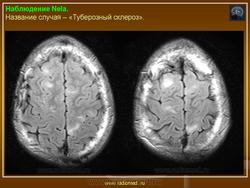

Туберозный склероз (болезнь Бурневилля-Прингла, синдром Бурневилля - Брессау) - глиоз белого вещества мозга, проявляющийся в раннем детстве эпилептическими припадками (в 85%), олигофренией в сочетании с нараста­ющей пирамидной и экстрапирамидной симптоматикой, кожной патологией. В возрасте 4-6 лет на лице в форме бабочки в области носа обычно появляют­ся множественные желто-розовые или коричнево-красные узелки диаметром чуть больше 1 мм - аденомы Прингла, которые обычно признаются аденомами сальных желез, однако есть мнение и о том, что они представляют собой про­исходящую из нервных элементов кожи гамартрому.

На поверхности мозга наблюдаются единичные или множественные глиома-тозные узлы, по цвету несколько светлее окружающего мозга и плотнее его на ошупь, возможна их кальцификация. Узлы могут быть и в белом веществе, под­корковых ганглиях, а также в стволе мозга и в мозжечке.

Встречаются и аномалии развития извилин мозга в виде микро- и пахигирии. Заболевание чаще носит спорадический характер. Бляшки достигают диаметра 5-20 мм. В коре больших полушарий и мозжечка иногда могут быть обнару­жены пластинчатые тельца, напоминающие амилоид. Происходит дегенерация клеток коры. При КТ-исследовании головы нередко можно выявить кальцифика-ты и глиальные узелки в паравентрикулярной области, субэпендимарно вдоль на­ружных стенок боковых желудочков, в зоне межжелудочкового отверстия Мон­ро, реже - в мозговой паренхиме. На М РТ головного мозга в 60% выявляются гипотеденсивные очаги в одной или обеих затылочных долях, которые расце­ниваются как участки неправильной миелинизации (Козлов А.В., 2002).